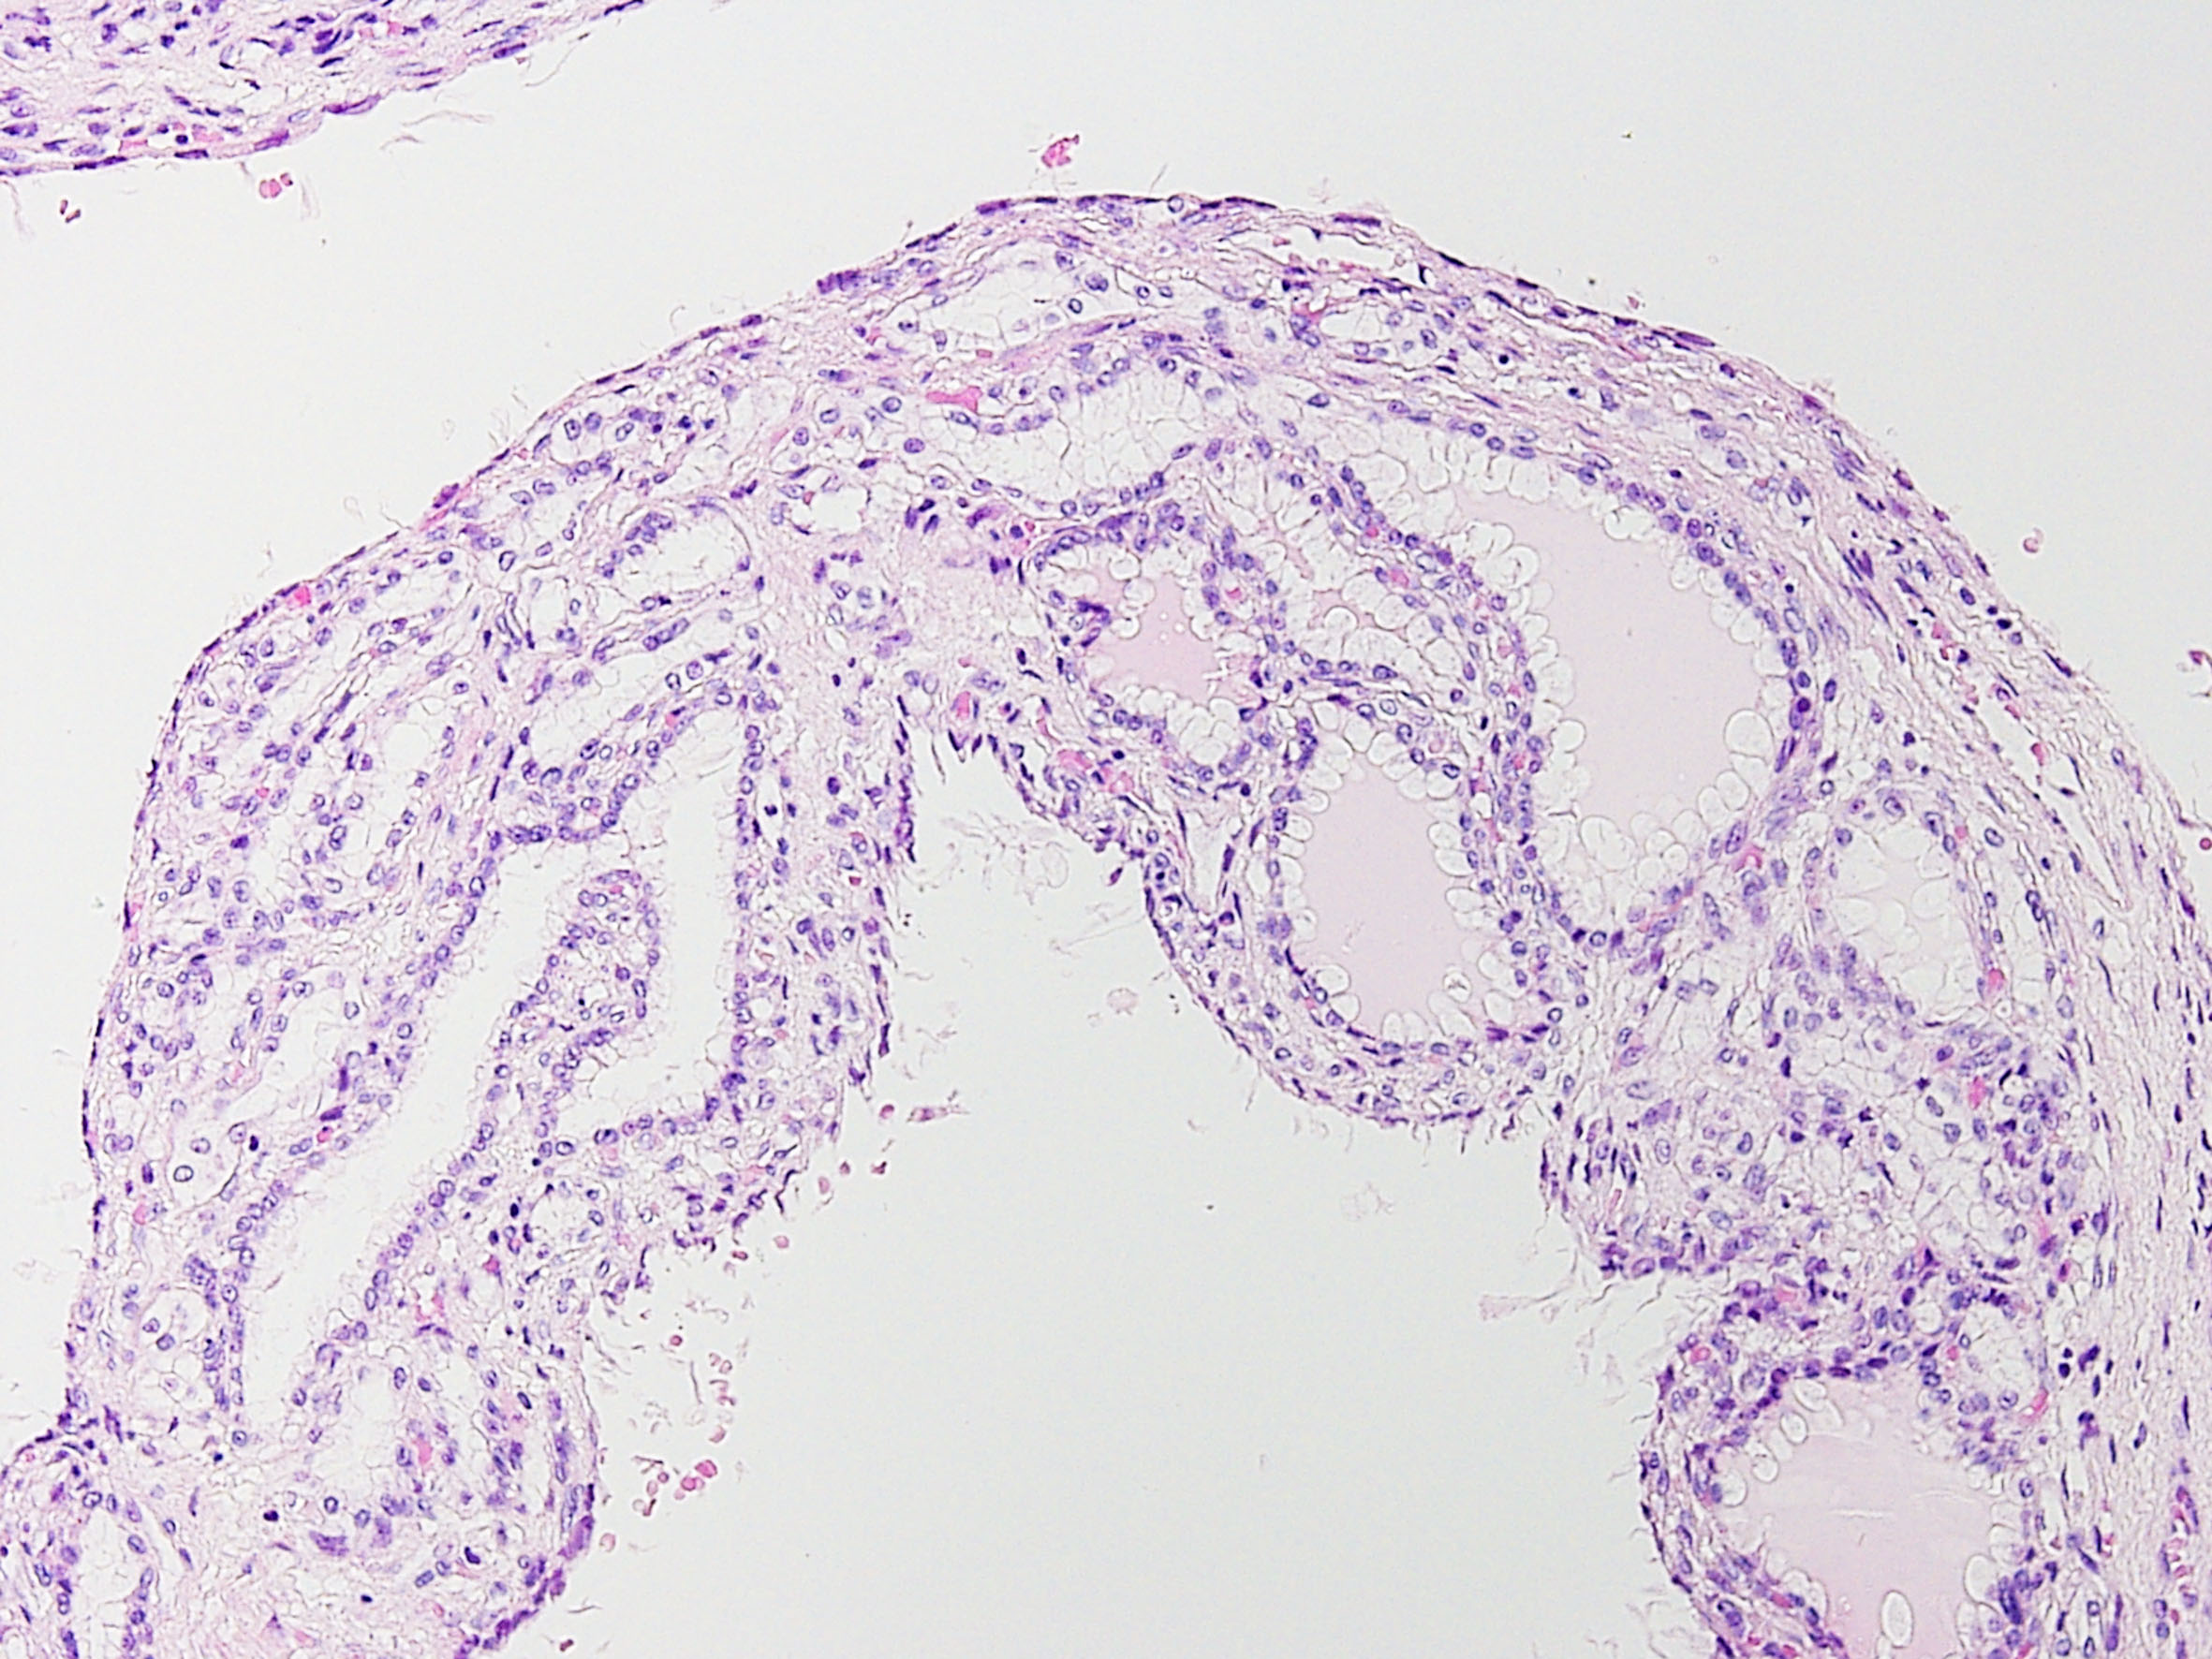

Consensus grade: Multilocular cystic renal neoplasm of low malignant potential

Multilocular cystic renal neoplasm of low malignant potential